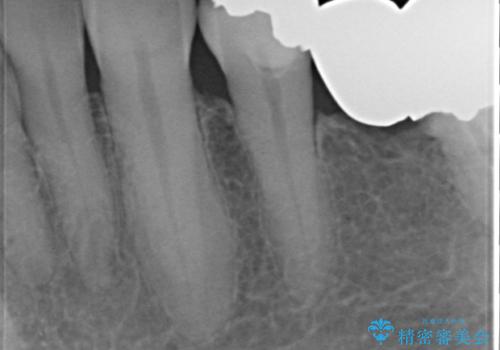

奥歯2本は虫歯により残っている健全歯質が少ないため、保存が難しい状態でした。

長期的な予後を保証できないことをご了承頂いた上で、歯根分割術、骨外科手術により歯の保存を試みました。

虫歯を丁寧に除去した後に歯根を分割し、骨を削合して健全歯質を露出させる骨外科手術を行いました。